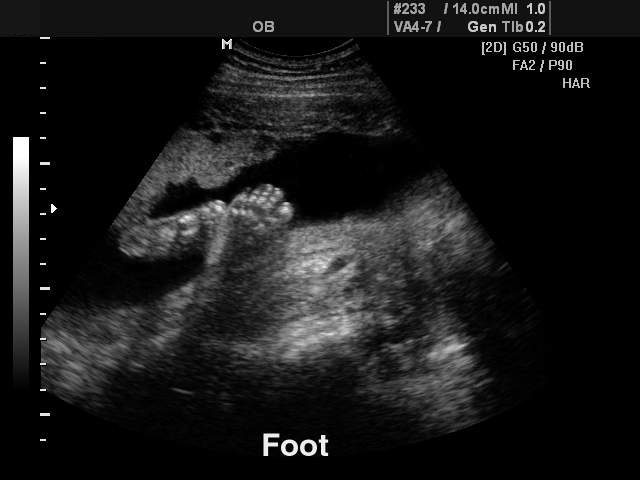

Fetal foot, B-mode

Fetal foot, B-mode (echogramm №123)

Echogramm was received by ultrasound scanner SonoAce-8000 (out of production).